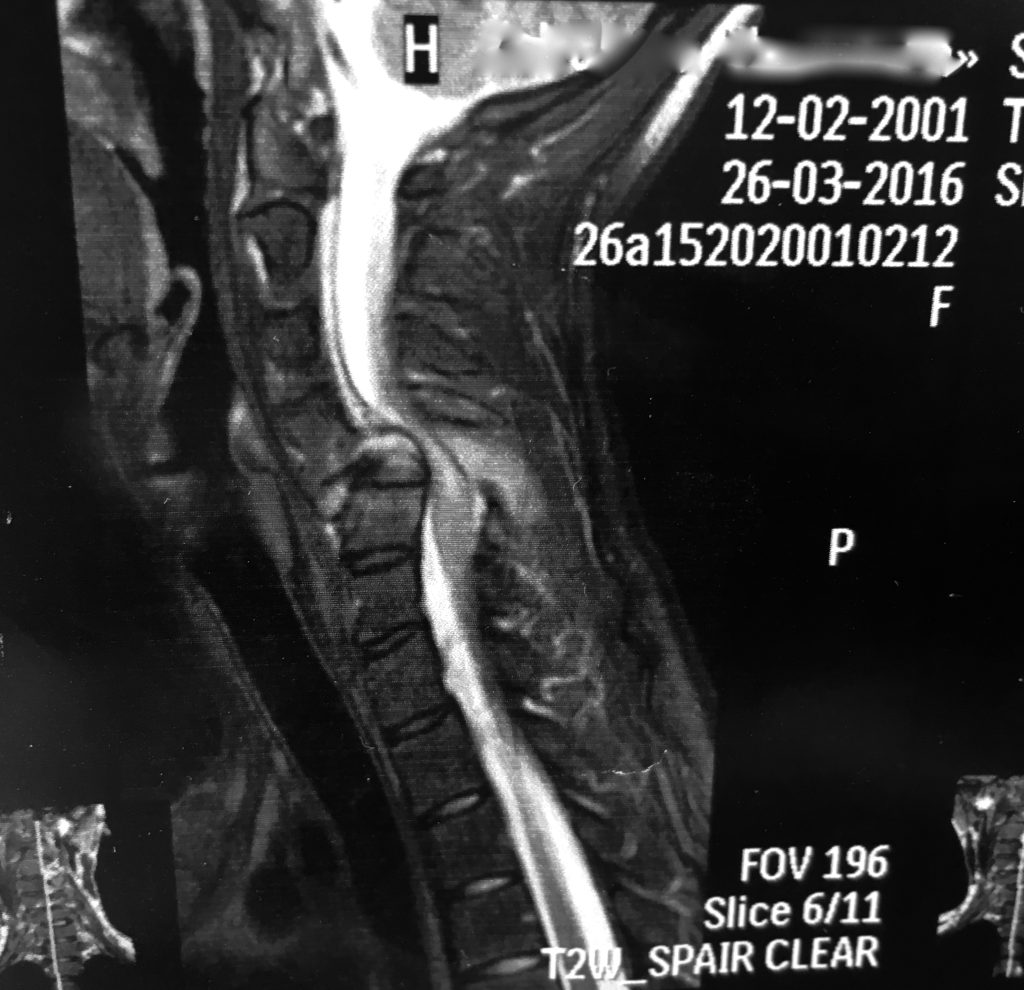

Види деформацій залежать від конкретної ділянки хребта, де відбуваються дегенеративні процеси — шийного, грудного або поперекового відділів хребта. Наявність або відсутність ускладнень, зокрема пролежнів та травм спинного мозку, відіграє важливу роль у визначенні ступеня посттравматичної деформації.

Клінічна картина патології

Головна ознака розвитку посттравматичних деформацій хребта – біль, що відчувається пацієнтом у спині, а пік її прояву спостерігається у тому відділі, де відбувається патологічний процес. Згодом пацієнт, у якого больовий синдром слабо виражений, тому залишається без належної уваги, починає відчувати труднощі в рухах, які стають дедалі скутішими і призводять до посилення болю.

Не виключається поява спастики у кінцівках. При деформації грудного відділу хребетного стовпа можуть виникнути проблеми з диханням, порушується робота серцево-судинної системи.

Через больовий синдром людина не може протягом тривалого часу утримувати хребет у вертикальному положенні. З розвитком патології біль посилюється і стає яскраво вираженим. Під час клінічного огляду спостерігається напруга паравертебральної мускулатури.

Посттравматичні деформації хребта неминуче призводять до порушення роботи інших органів прокуратури та систем, особливо страждає центральна нервова система. Ситуація може посилюватися стисненням спинного мозку, внаслідок чого виникають незворотні процеси неврологічного характеру.

У більшості випадків у пацієнта спостерігаються порушення функції сечостатевої системи, парези і паралічі в кінцівках. При деформації у шийному відділі хребта пацієнт може відчувати часті головні болі, зниження гостроти зору. Якщо зачеплений спинний мозок, виникають важкі патології, які без надання своєчасного лікування мають незворотний характер.